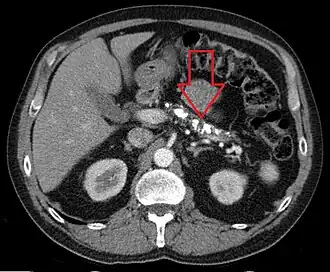

![]() TC axial que muestra múltiples calcificaciones en el páncreas en un paciente con pancreatitis crónica | ||

El diagnóstico de la pancreatitis crónica es difícil. Los análisis de sangre habitualmente no son útiles. Las pruebas diagnósticas más importantes son las de imagen.[6][7] La presencia de calcificaciones pancreáticas en una radiografía simple de abdomen es diagnóstico de pancreatitis crónica pero lo más frecuente es que no se vean. Existen muchas otras pruebas de imagen que nos permiten llegar al diagnóstico: ecografía, tomografía axial computarizada y resonancia magnética del abdomen, endoscopia digestiva con inyección de contraste en el páncreas (colangiopancreatografía retrógrada endoscópica o CPRE) o ecografía a través de endoscopia digestiva (ecoendoscopia). Existen otras pruebas que sirven para medir la capacidad de funcionamiento del páncreas.